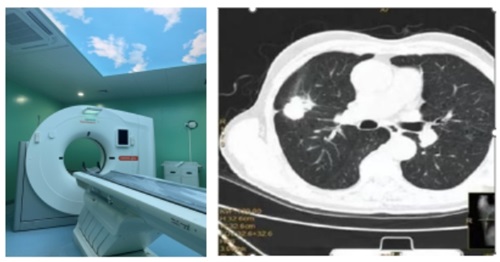

如何进行肺癌筛查?

肺癌筛查很简单,但并不是所有的人都需要进行肺癌筛查,指南建议50-74岁的人群为重点筛查人群。对于75岁及以上的老年人可以考虑机会性筛查。需要结合年龄、是否吸烟和是否有高危因素来判定是否是肺癌高危人群和具备肺癌危险因素,如果具备,就需要去医疗机构去进行低剂量螺旋CT检查。

拿到CT报告单,如果看到钙化结节、纤维条索,大家不用太担心,多数是既往肺部病灶遗留的陈旧性病变或瘢痕。筛查或体检发现的肺部结节绝大多数是良性结节,大家不必看到结节就恐慌。如果结节大小6mm以下,可以不用太担心。如果结节大小6mm以上,建议到医院呼吸专科或胸外科就诊,听从医生的专业建议。